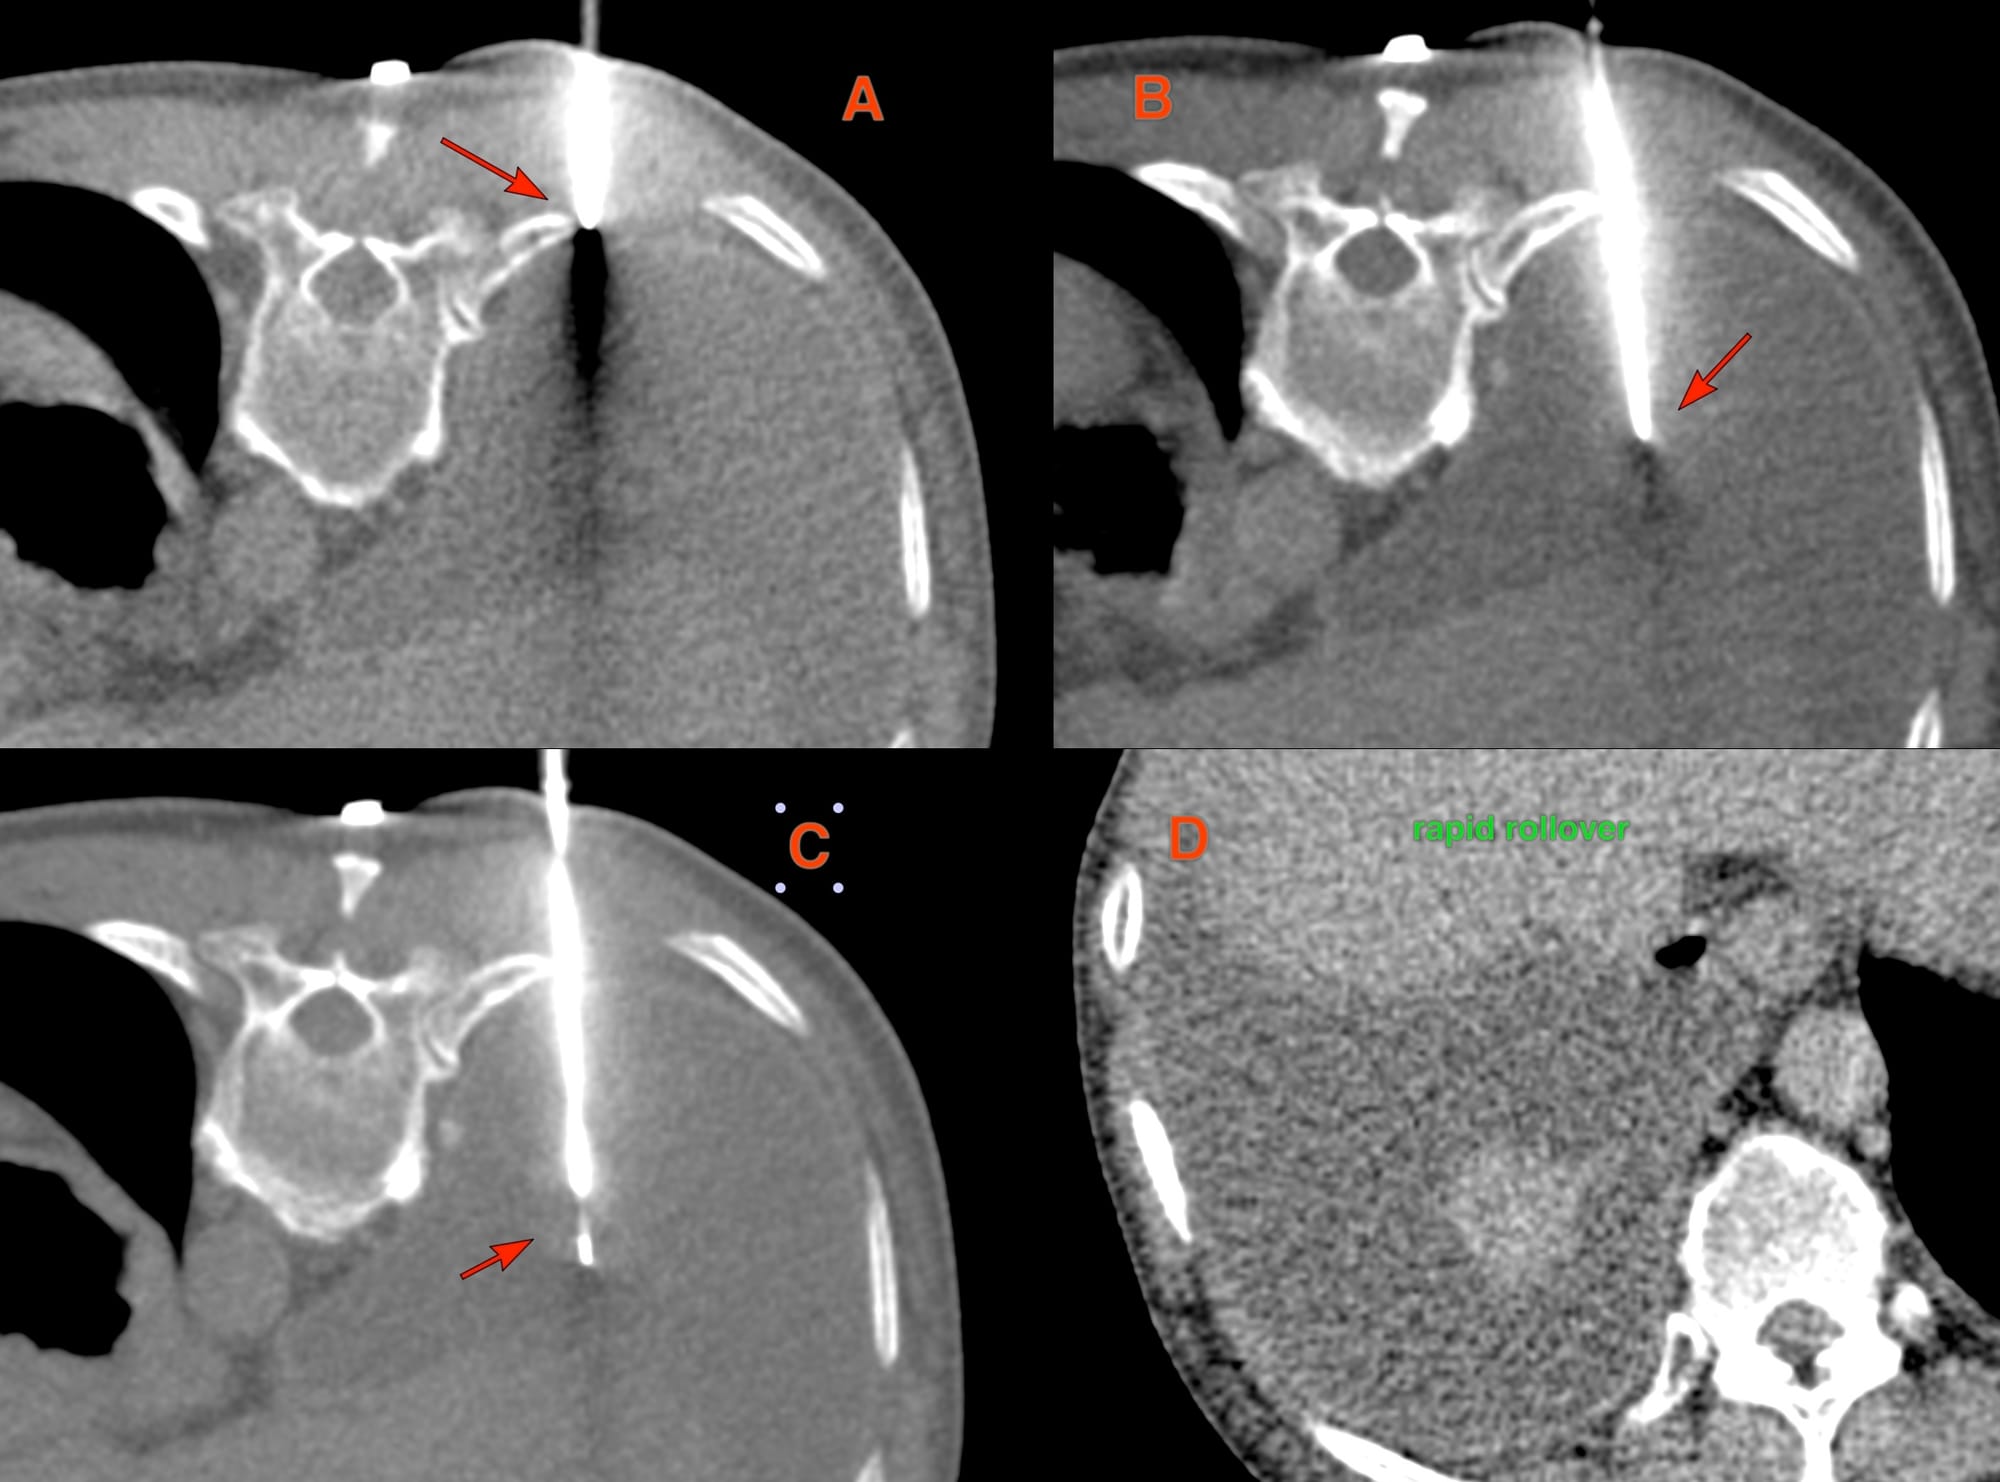

The patient was referred for a CT guided biopsy.